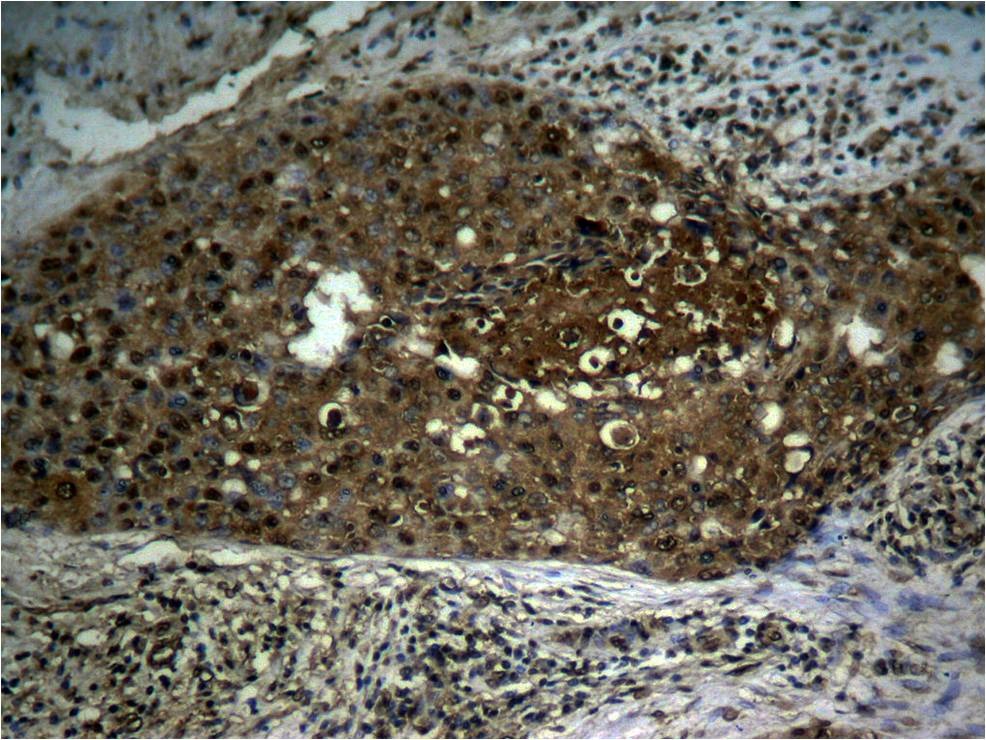

3. Immunohistochemical analysis of paraffin-embedded human breast carcinoma tissue using NFκB-p65 (Phospho-Ser276) Antibody TMAC-02836 (left) or the same antibody preincubated with blocking peptide (right).

4. Immunohistochemical analysis of paraffin-embedded human breast carcinoma tissue using NFκB-p65 (Phospho-Ser276) antibody TMAC-02836.